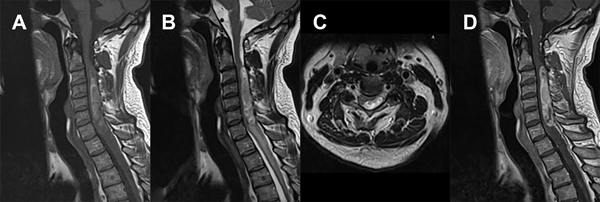

En el estudio de RM de encéfalo con contraste se describe atrofia del parénquima cerebral de forma generalizada asociado a hidrocefalia ex vacuo, sin otra aclaración a destacar. A nivel de la RM cervical con contraste se observa lesión ocupante de espacio intradural intramedular con extensión desde C3 a C7 de 12.2 mm x 9.7 mm x 20.7 mm, con efecto de masa sobre el tejido medular espinal en dichos niveles, comportándose como hiperintensa tanto en T1 como en T2, con captación tras la inyección del medio de contraste, sin evidencia de edema perilesional (Figura 1).

Figura 1. RM de columna cervical. A) Secuencia T1. Corte sagital. B) Secuencia T2. Corte sagital. C) Secuencia T2. Corte axial. D) Secuencia T1 con contraste. Corte sagital.